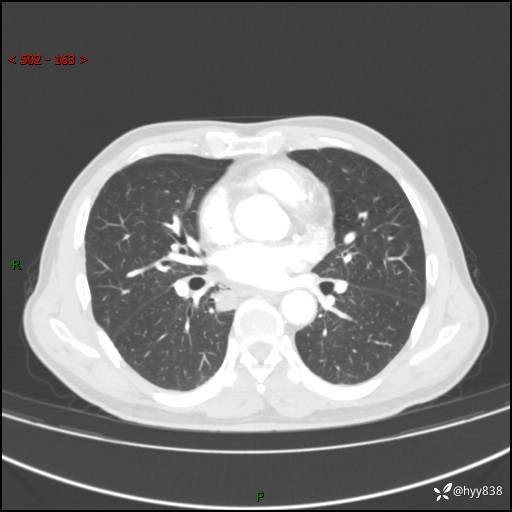

69岁/男,发现肺部病变6天。该有的征象都有,肉芽肿 VS 肿瘤,一念之间---(有结果)

主诉:发现肺部病变6天。

现病史:患者6天前于我院泌尿外科住院,住院期间行胸部CT检查,提示“肺部病变”,患者无畏寒、发热、盗汗、咳嗽、咳痰、咯血、胸痛、呼吸困难,无反酸、腹痛、腹泻、头痛、头晕等不适。未予特殊处理,现为进一步诊治,门诊以“肺肿物”收入我科。 患者本次起病以来,精神食欲尚可,大小便正常,体力及体重无明显变化。

胸部CT平扫+增强